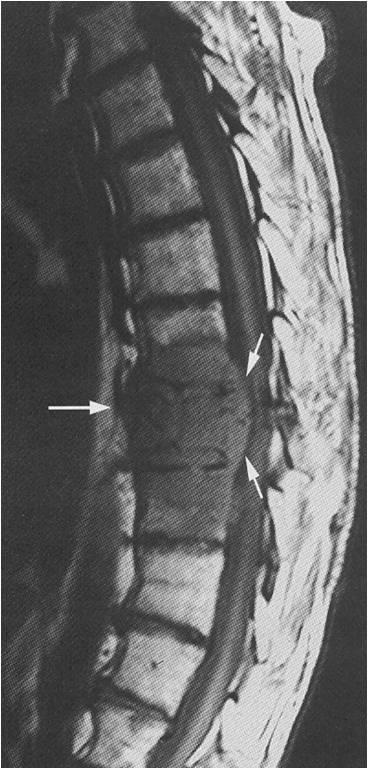

Mágneses rezonancia képalkotás segít a diagnózis traumás sérülések akut és hosszú távon. Amikor tömörítés az ágyékcsigolyák és törések megfigyelt csökkenése a magassága az érintett csigolya, atipikus visszhangjel a károsodási zóna.

A törések a keresztcsont meghatározott vonal zavarok csont integritását, a sejttörmelékek jelenléte és a csont fragmentumok. MRI gerinc végezzük pontos differenciálódása típusú törésre (vízszintes, függőleges, ferde, aprított) és annak szövődményei. Amellett, hogy a diagnózis csontdefektusok, egy MRI az ágyéki gerinc képes észlelni vérzés, kár, hogy az idegszövet és a környező lágy szövetek struktúrák.

Az akut fázisában vérzés T1-VI izointensivnoe festéssel, és a T2-VI - hiperintenzív. A távoli időszakban (2 héttel később) a T2-VI kandalló magas jel erősségének a kontúr a periféria hypointense (hypointense RIM vastagsága függ a kortól sérülés).

Amikor inramedulyarnom folyamat miatt túllépik gerincvelő sérülés Nyílásméretek, perifocal ödéma jelen. A T2-súlyozott MRI képek a gerinc kandalló magas jel intenzitását. Amikor egy kontrasztanyag, a tumor láthatóvá jobb kontraszt felhalmozódása.

Amikor ekstramedulyarnom kandalló elrendezés alakul tömörítés a gerinccsatorna és annak tartalmát. A tumor maga formájában Tomográfia uzlopodobnogo képződését változó jel intenzitását.